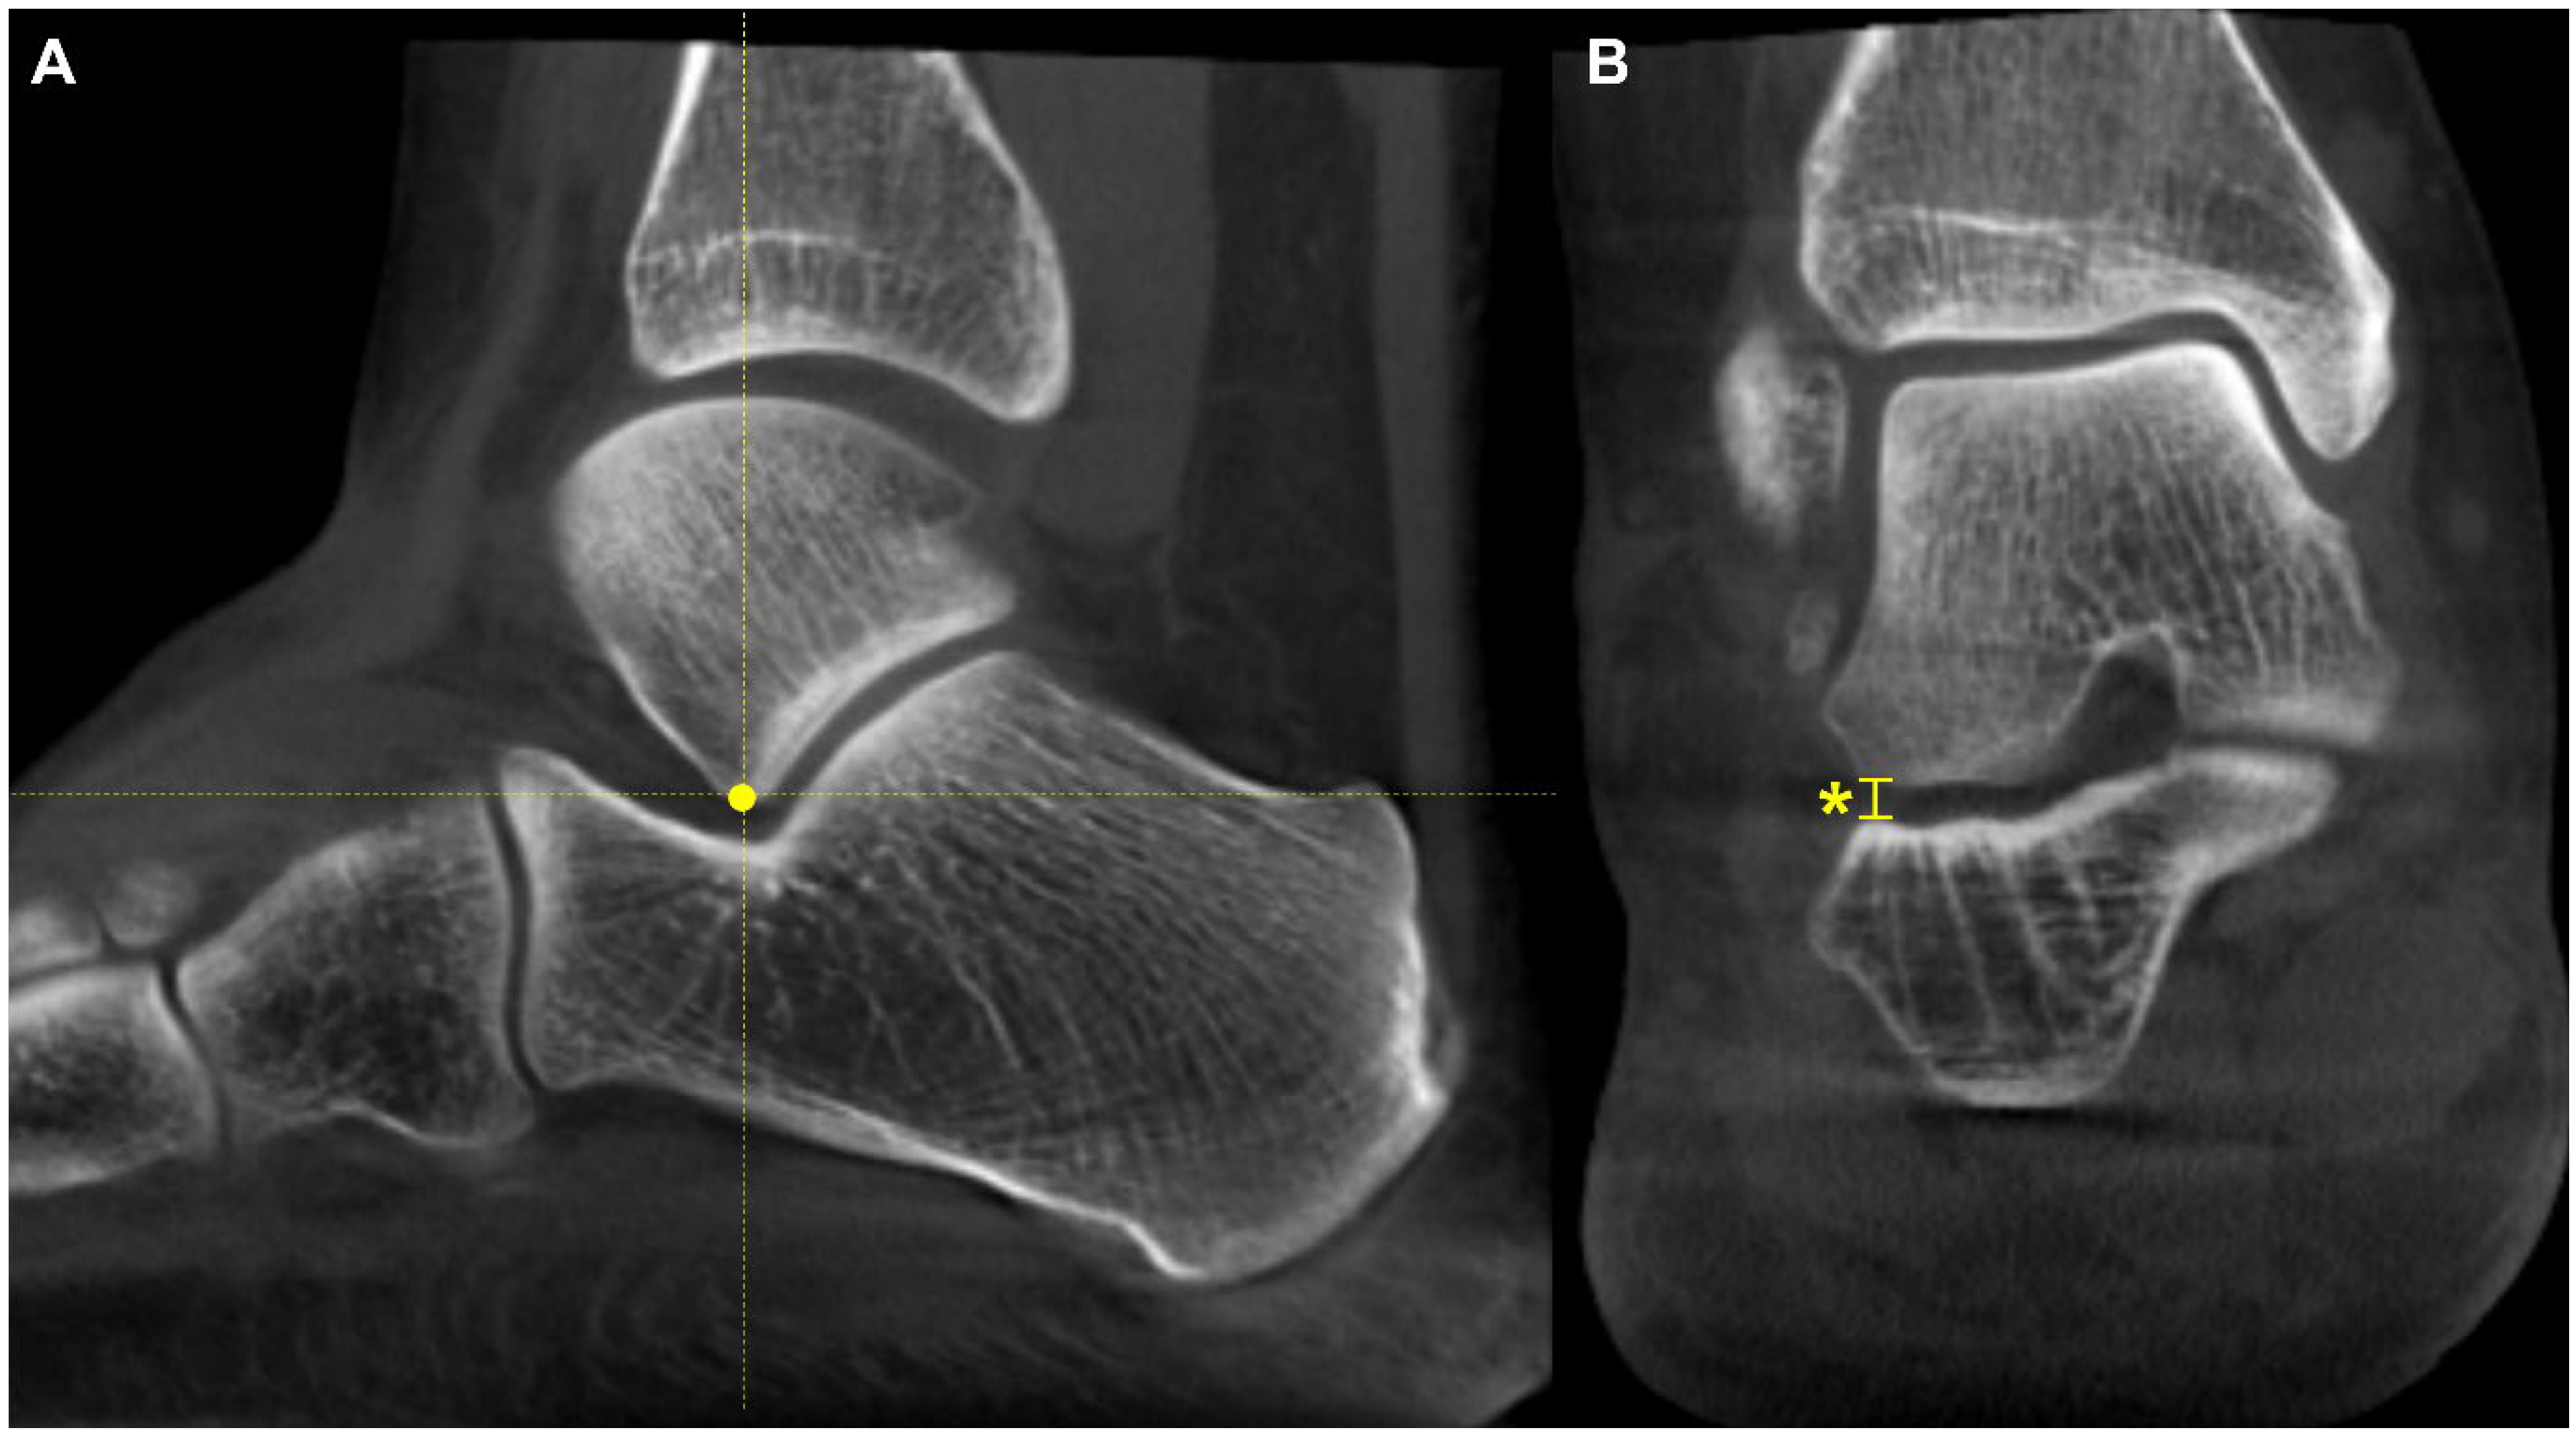

The talonavicular coverage angle is also used in WBCT as an indicator to assess midfoot abduction [36]. In fact, a new classification system for PCFD includes sinus tarsi impingement as one of the findings of midfoot abduction. Sinus tarsi impingement, which commonly causes lateral hindfoot pain, is caused by bony contact between the talus and calcaneus and should be addressed when establishing a therapeutic strategy in PCFD [42]. Because of superimposition effects, however, sinus tarsi impingement is difficult to identify using conventional radiographs. Instead, WBCT allows for the identification of bony impingement in a physiological standing position. Kim et al. devised a novel method to measure the talocalcaneal distance, which features realignment of the coronal and sagittal planes to directly trace the inferior border of the lateral process of the talus [43] (Figure 8). The inferior border of the lateral process of the talus is chosen to reconstruct the coronal reference plane because it is a constant anatomical landmark to obtain minimal talocalcaneal distance. Using this method, the authors investigated the correlation of talocalcaneal distance narrowing with common radiographic parameters on standard weight-bearing radiographs. They observed that talocalcaneal narrowing correlated most with talonavicular coverage, with a cutoff value of 41.2 degrees. Andres et al. conducted a comparative study to identify whether there is an association between WBCT-based measurements and MRI findings [44]. They found that MRI findings overestimate the presence of bony sinus tarsi impingement in approximately 42% of the included population and concluded that WBCT would be a better diagnostic option to detect bony impingement in PCFD.

Figure 8.

Talocalcaneal distance. (A) Using the sagittal view for reference, the most inferior point of the lateral process is identified. (B) At this point, the narrowest distance between the inferior border and the calcaneal floor is measured in the selected coronal slice (Asterisk).